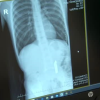

İSTANBUL - Beylikdüzü'nde 9 yaşındaki çocuk oyuncak olarak satılan stres bilyeleri olarak da bilinen neodyum adlı güçlü mıknatıstan 42 adet yuttu. Kusma karın ağrısı şikayetiyle hastaneye getirilen çocuğun röntgen filmi çekilince gerçek ortaya çıktı. Ameliyata alınan çocuğun delinen bağırsağından mıknatıslar çıkarıldı. Beylikdüzü'nde 9 yaşındaki bir çocuk ailesinin haberi olmadan neodyum adı verilen stres bilyeleri olarak da bilinen 42 adet mıknatısı yuttu. Birkaç gün sonra şiddetli karın ağrısı ve kusma şikayeti ile hastaneye gelen çocuğun röntgeni çekildi. Röntgen filminde çocuğun midesinde boncuklar halinde yabancı bir cisim tespit edildi. Bağırsağını delen cismi fark eden Beykent Üniversitesi Çocuk Cerrahisi Uzmanı Prof. Dr. Ali Çay çocuğu ameliyata aldı. Yapılan ameliyatta çocuğun bağırsaklarından rengarenk şekilde 42 adet neodyum çıkarıldı. "Tesadüfen bu mıknatısları yuttuğunu biz radyografide gördük" Konuyla ilgili konuşan Prof. Dr. Çay, yutulan cisimlerin normalde sindirim sistemi ile çıkabileceğini ancak çoklu mıknatısların bağırsaklarda delinmeye neden olabileceğini ifade ederek, "Bizim hastamız yaklaşık 42 tane bu mıknatıstan yutmuş çeşitli hastanelere müracaat etmiş. Burada yapılan incelemelerde çekilen filmlerde tesadüfen bu mıknatısları yuttuğunu biz radyografide gördük hastamızı ameliyata aldık. İnce bağırsak uç kısmında delinme oluşturmuştu. Biz bu mıknatısları çıkardık" dedi. "Hayatı tehdit eden bu tür oyuncakları çocuklardan uzak tutmaya önem gösterelim" Çocuklar tarafından bu mıknatısların çok yaygın oynandığını kaydeden Çay, "Böyle renkli ve göz alıcı mıknatıslar çok güçlü mıknatıslar aynı zamanda. Bunlar ciddi anlamda problem oluşturuyor. Yabancı cisimlerin yüzde 1'inde cerrahi komplikasyon oluyor. İnşallah bundan sonra yaraları iyileştikten sonra yakın olarak takip ediyoruz. Herhangi bir kalıcı problem olmayacak. Bu mıknatısları çocuklar çok yaygın kullanıyor. Bu mıknatıslar çok kuvvetli çok tehlikeli. Hayatı tehdit eden bu tür oyuncakları çocuklardan uzak tutmaya önem gösterelim" diye konuştu.